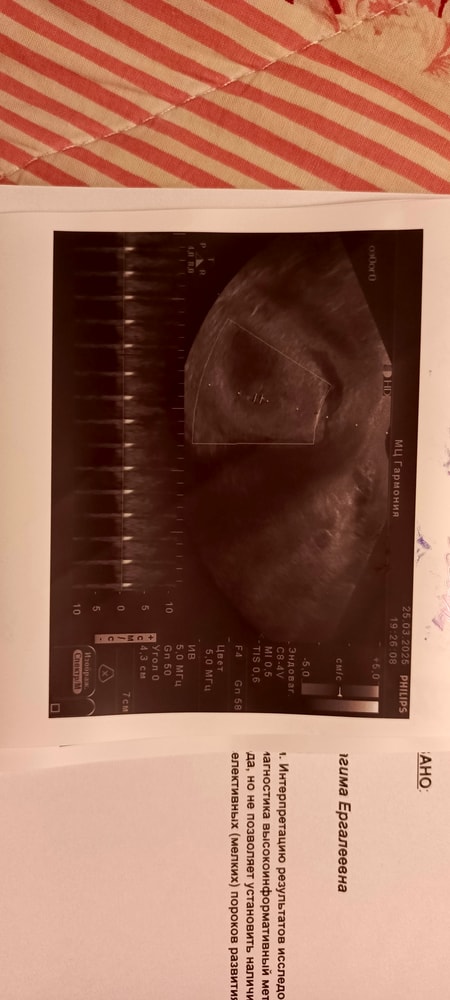

Вторая полость в матке. Двурогая матка?

Ну, вижу перегородку тоже Попробуйте переделать УЗИ у еще специалиста, моей маме сказали про двурогость когда она забеременела только младшей сестрой моей, а у меня еще старшая и я)) у меня двурогость, обратили сразу при первом обследовании

Lisa, не переживайте, снимки не четкие, одна полость, одно плодное яйцо. Перегородка она при двурогой матке есть У вас нет, сравнила свои снимки, у вас не так

Alenchik, прикрепила в исходное сообщение фото узи

Наше узи Размер плода 16+5